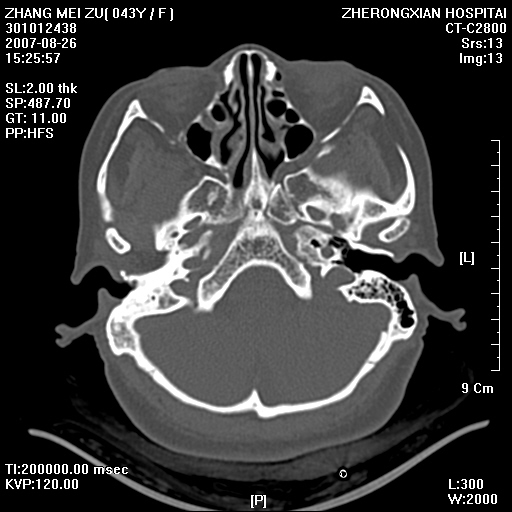

标题: CT9512:F43Y,是肉芽肿还是胆脂瘤?诊断报告该如何出? [打印本页]

标题: CT9512:F43Y,是肉芽肿还是胆脂瘤?诊断报告该如何出?

右耳硬化性乳突炎并鼓窦入口胆脂瘤形成,左侧乳突炎

典型胆脂瘤,从上鼓室,乳突窦入口到乳突窦有明显光滑的骨质破坏和软组织结节均为胆脂瘤特点.而肉芽肿对骨质的破坏是轻微的.值得关注的是乳突后壁被破坏只剩薄薄的一层,如果再不尽快治疗,胆脂瘤如果突破其后壁即可能形成耳源性脑脓肿了.